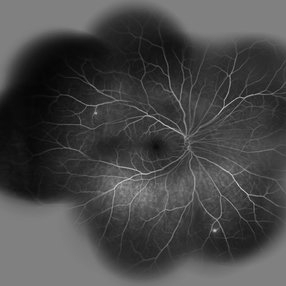

Behcet's Disease Behcet's DiseaseMar 13 2013 by Hamid Ahmadieh, MD Wide field FA of the right eye of a 23-year-old man with retinal vasculitis and branch retinal vein occlusion (BRVO) due to Behcet's disease . Photographer: Solmaz Shahmohammad, Negah Eye Center, Tehran Imaging device: Heidelberg Spectralis Condition/keywords: branch retinal vein occlusion (BRVO), retinal vasculitis